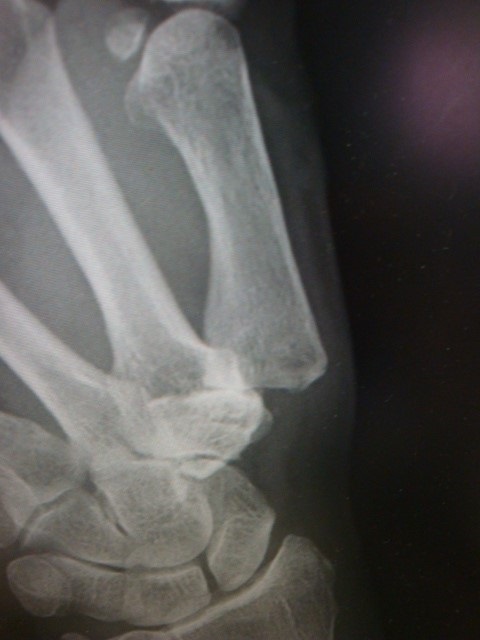

![]() |

母指の付け根の部分の痛みで、進行すると見た目も変形してきます。 原因は関節の変形によるものです。 最初は瓶のふたを時のような力を入れる動作で痛みを自覚し徐々に軽作業でも痛くなります。 初期の場合は安静固定をするだけで、症状は軽くなりますが、痛みが強い場合、関節注射や装具療法を行います、さらに仕事や日常生活に支障をきたすようなケースでは手術療法を行うこともあります。 |